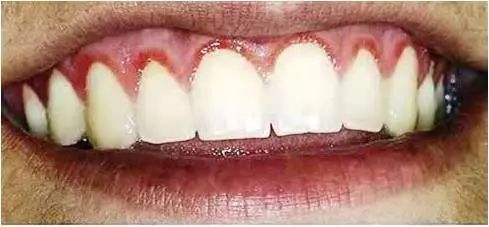

牙龈线形红斑

特征性的表现是沿着牙龈边缘分布的界限清晰的火红色改变,看起来很像 “纹”出来的“牙龈线”,实为牙龈充血。与一般牙龈炎症导致的牙龈充血不同,它的病因并非牙菌斑,患者通常口腔卫生状况良好,很少甚至没有牙菌斑。